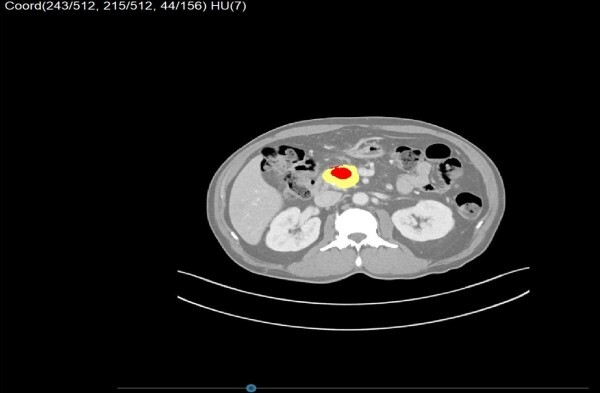

| ▲ CT 데이터를 기반으로 병변(붉은색)과 주요 장기(노란색)를 AI가 자동 구분한 3D 영상 (사진=엠에스병원 제공) |

MEDIP PRO는 기존 CT 단면 영상 데이터를 기반으로, AI가 자동으로 장기와 병변을 분리하고 이를 입체적으로 재구성하는 3D 영상화 시스템이다. 특히 환자의 갈비뼈, 골반뼈 등 골격구조를 기준으로 병변의 위치를 정밀하게 재현할 수 있어, 고주파온열치료와 같은 해부학 기반 국소치료의 타켓팅 정확도를 개선할 수 있다는 평가다.